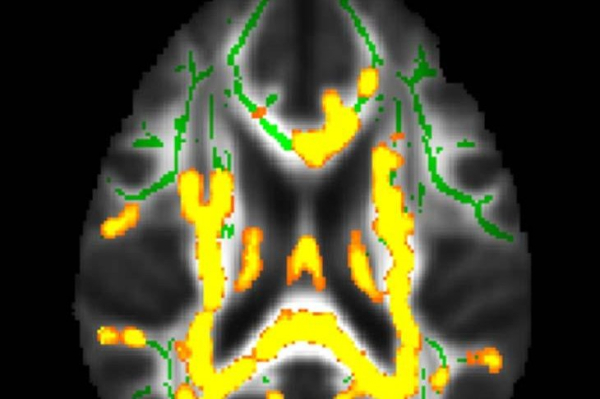

1 of 2 | This image showed increased neuroinflammation (yellow colors) with higher hidden fat in the brain’s white matter in the cohort of participants with an average age of 50 years. The green colors are normal white matter. Photo by Dr. Mahsa Dolatshahi/Radiological Society of North America

Visceral abdominal fat, which has been linked to Alzheimer’s, is the fat surrounding the internal organs deep in the belly. Researchers found that this hidden fat is related to changes that occur in the brain up to two decades before the earliest memory loss symptoms of Alzheimer’s appear.

The volume of subcutaneous fat — fat under the skin — and visceral fat were measured using abdominal MRI. Brain MRI measured the cortical thickness of brain regions that are affected in Alzheimer’s disease.

Positron emission tomography, or PET, was used to examine disease pathology in a subset of 32 participants, focusing on amyloid plaques and tau tangles that accumulate in Alzheimer’s disease, the release said.